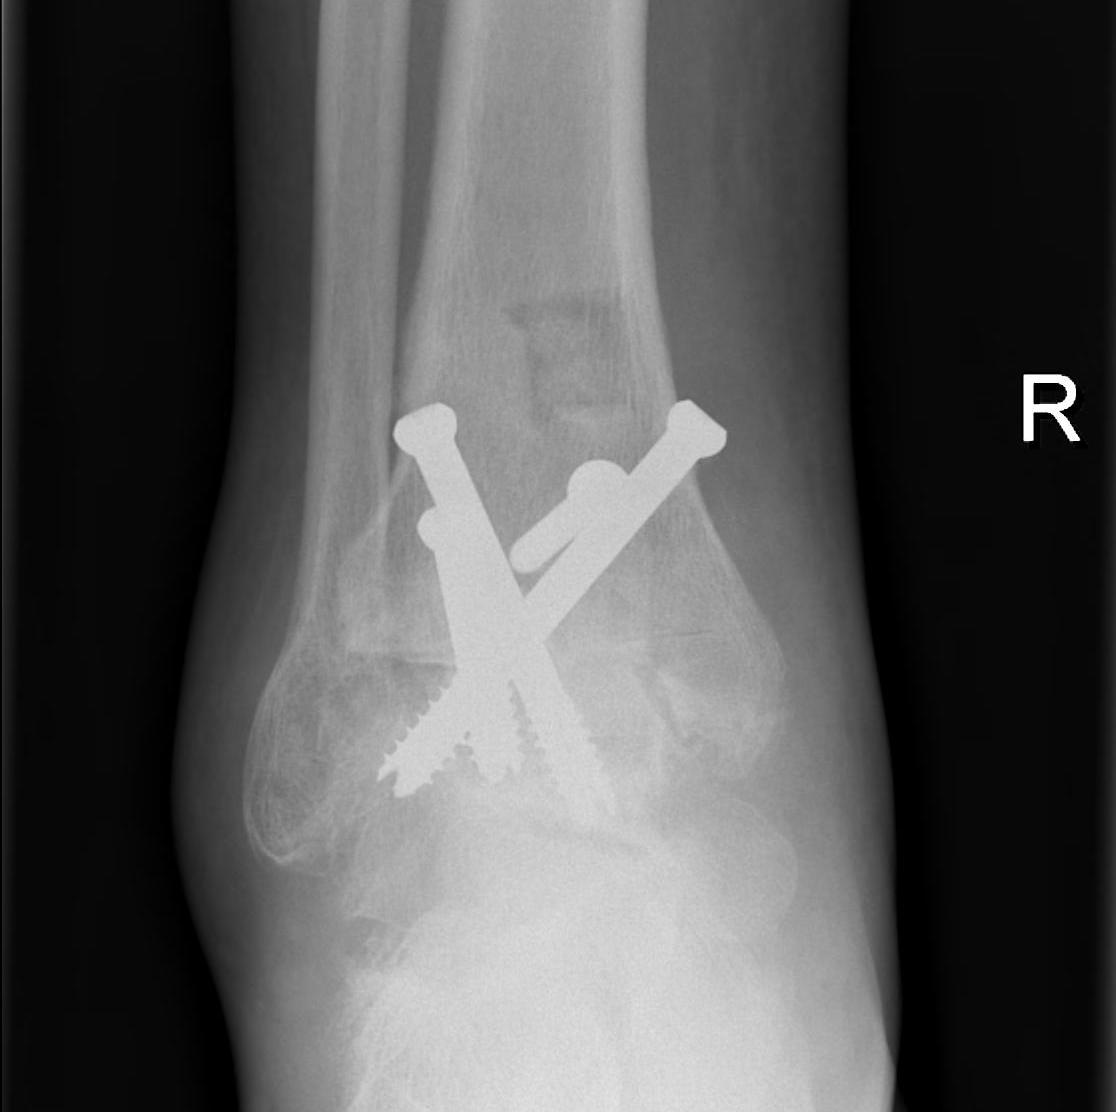

Pantalar fusion with hindfoot nail

talus avntalus AVNPantalar fusion